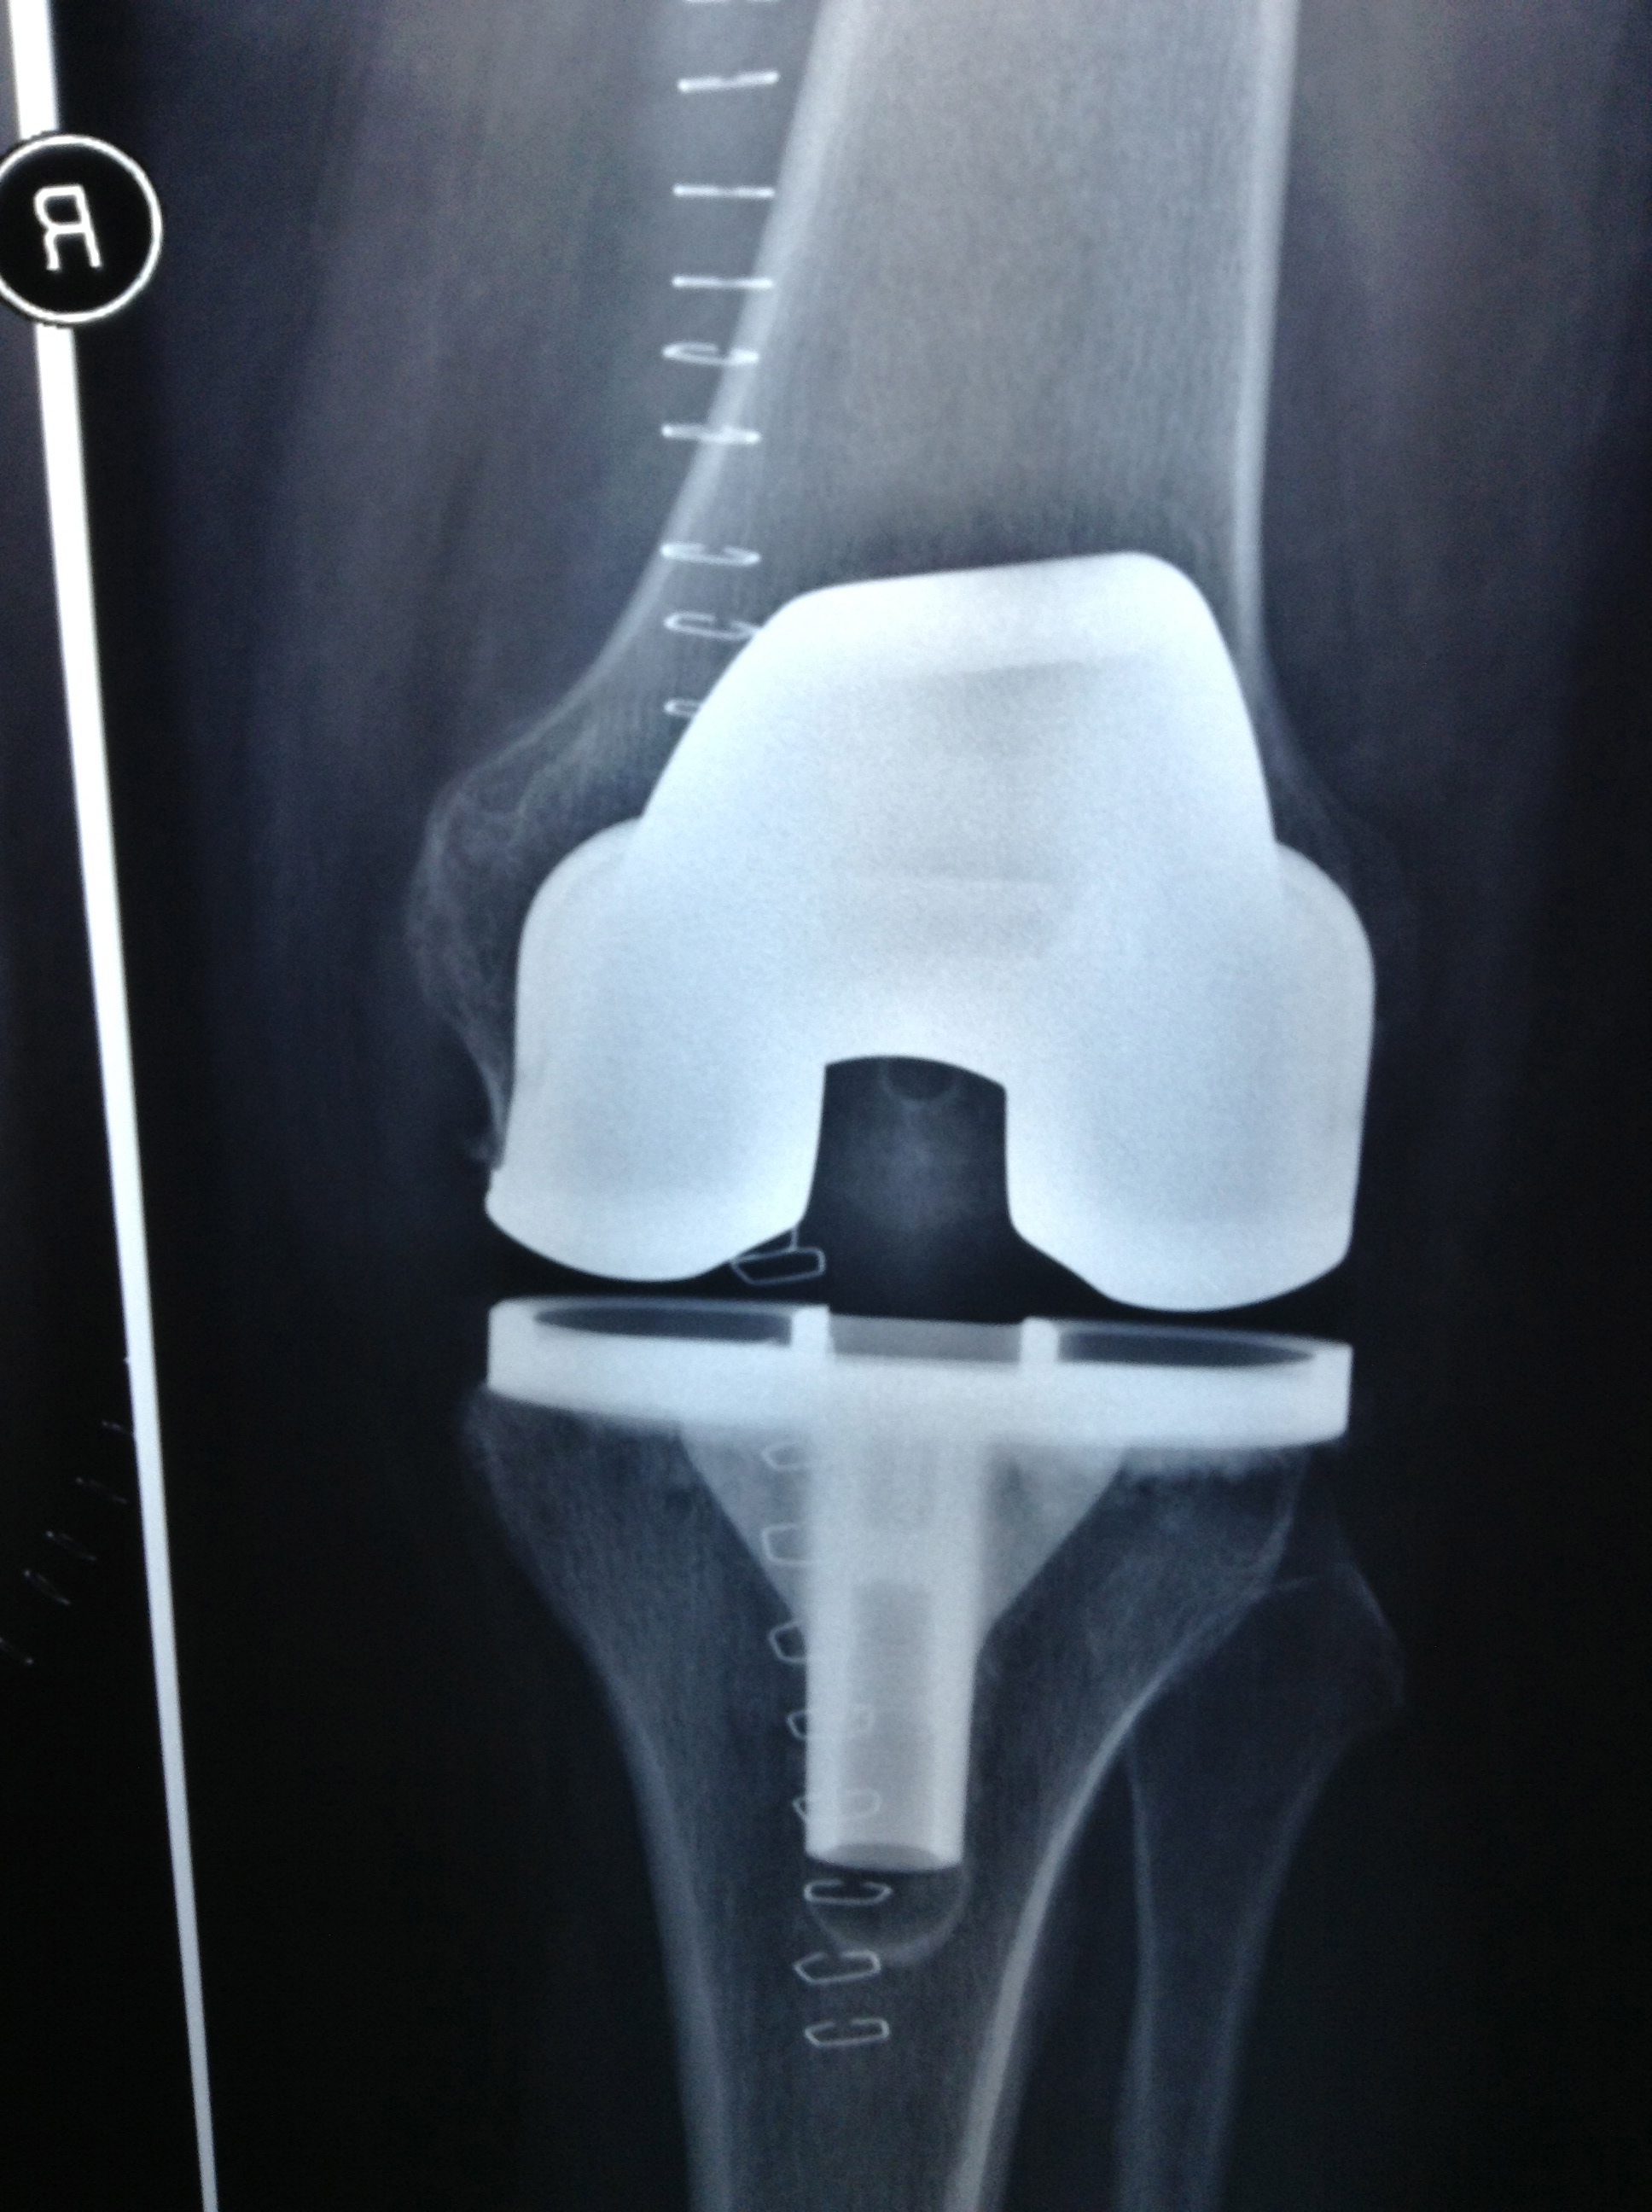

Revision Total Knee Replacement After Infection

• Revision Total Knee Replacement After Infection